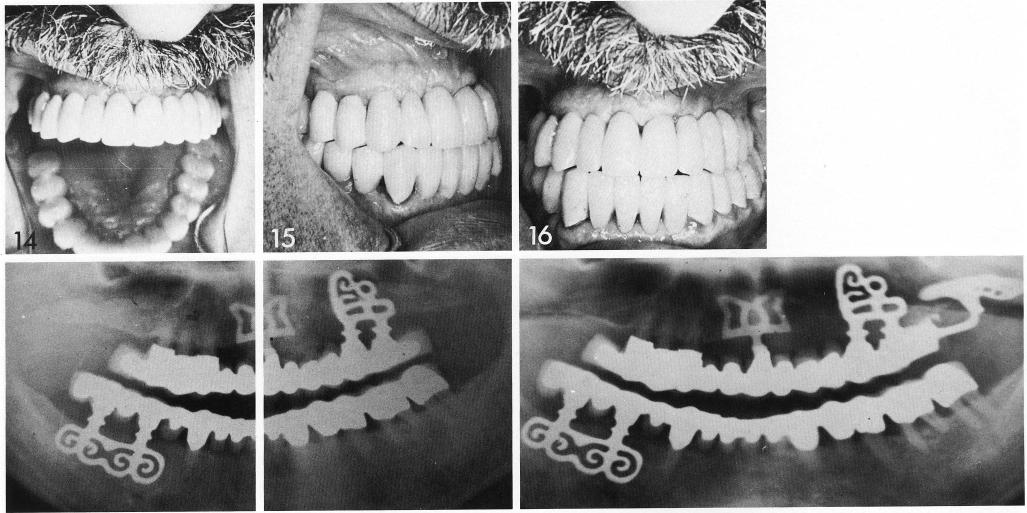

A synergistic response is achieved by using endosteal blades in the anterior region (5), after extraction of bayselers teeth. An additional sinus circumventing blade is used posteriorly. After healing (7), an impression is taken to fabricate the permanent anterior splint. After insertion (8), a pterygoid impression is taken (11). Subsequently this is inserted with an overlay porcelain-to-metal casting (12). A full arch fixed prosthesis results (14-16).

1 A maxillary full arch fixed prosthesis inserted over the implants